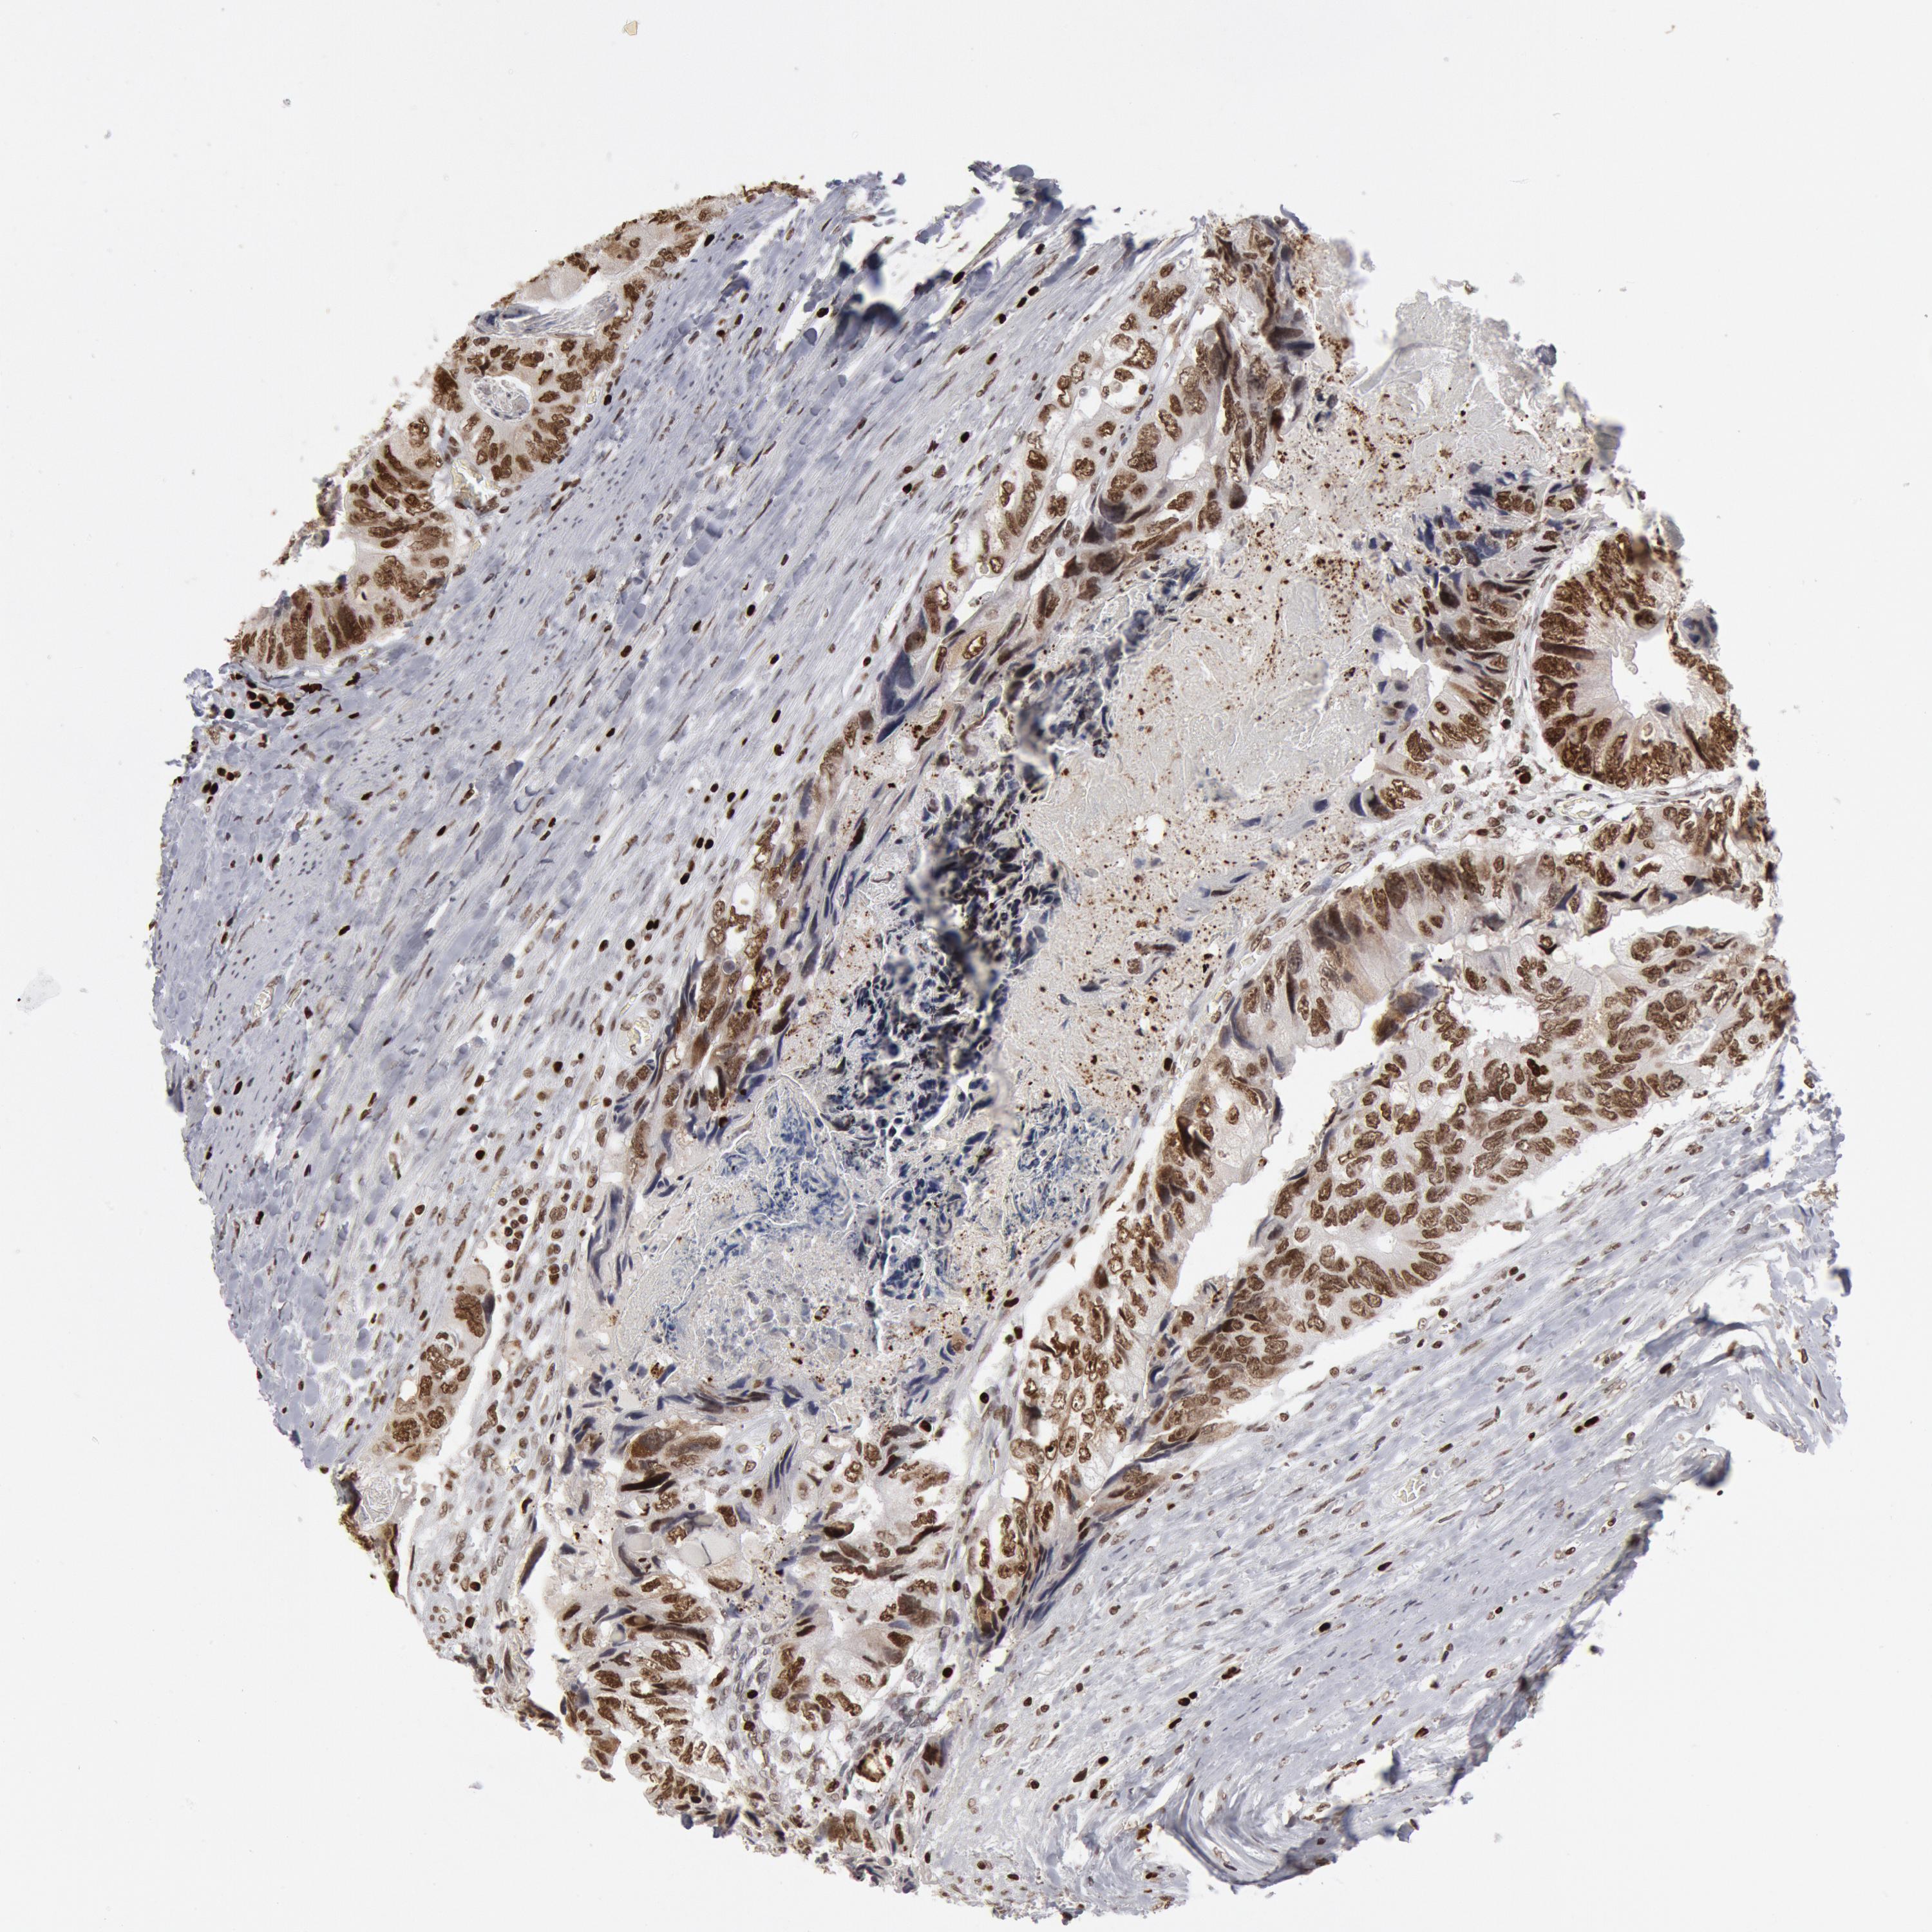

CANCER COLORECTAL CANCER Show tissue menu

Colorectal cancer

Human cancer

Colon adenocarcinoma

Rectum adenocarcinoma